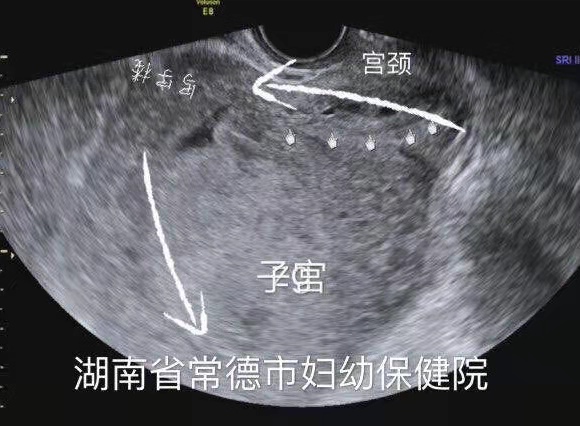

子宫明显后倾后屈,宫颈细长